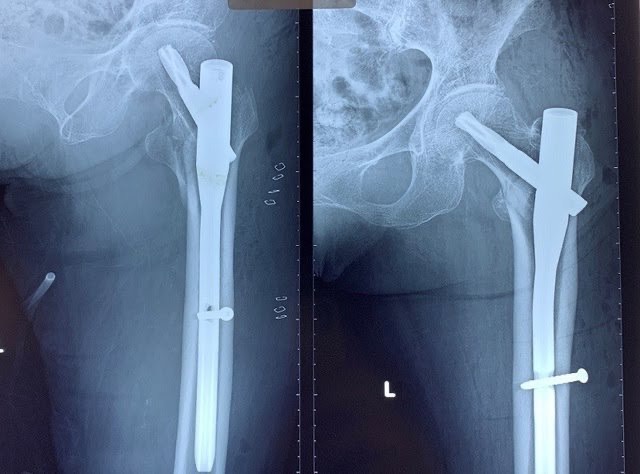

4.2. Điều trị phẫu thuật: Nếu không được điều trị phẫu thuật kịp thời bệnh nhân sẽ có những biến chứng nặng nề như: viêm phổi, viêm đường tiết niệu, đặc biệt gây loét các điểm tỳ và bệnh nhân sẽ tử vong do những biến chứng đó. Có nhiều chỉ định phẫu thuật khác nhau được đặt ra cho gãy LMC ở người cao tuổi như kết hợp xương ( đóng đinh nội tủy, nẹp DHS …), thay khớp háng. Mỗi phương án phẫu thuật có những ưu nhược điểm khác nhau.  Đối với các loại gãy LMC di lệch phân độ A2.2 và A2.3 ( theo Muller), gãy xương kèm theo tình trạng thoái hóa khớp háng từ trước hoặc chất lượng xương yếu do loãng xương không đủ độ chắc để có thể giữ vững được các phương tiện kết hợp xương bên trong hoặc trong trường hợp đã điều trị thất bại đối với các phương pháp kết hợp xương trước đó thì chỉ định thay khớp háng nhân tạo cho bệnh nhân cũng là một giải pháp tốt.